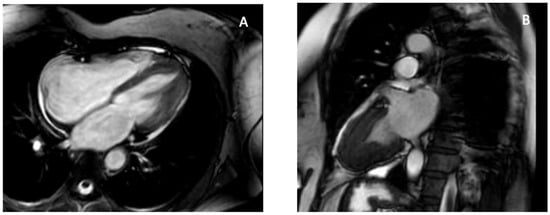

Apical hypertrophic cardiomyopathy (ApHCM), or Yamaguchi syndrome, was first reported in Japan in 1976 [44], and is defined by unexplained left ventricular hypertrophy predominantly involving the apex, with an end-diastolic apical wall thickness ≥15 mm [45]. Sarcomeric mutations in MYH7 and MYBPC3 are identified less frequently compared with other HCM subtypes and do not significantly affect clinical outcomes [46]. Clinical presentation ranges from asymptomatic to chest pain, dyspnea, or syncope, and myocardial ischemia may result from apical hypertrophy, microvascular dysfunction, and increased intracavitary pressures. Apical aneurysms develop in up to 13% of patients and are associated with arrhythmic and thromboembolic risk [47,48]. TTE is the first-line modality for diagnosis and follow-up [11]. ApHCM typically lacks septal hypertrophy or systolic anterior motion—features that distinguish it from classic HCM—and is generally not associated with LV outflow tract obstruction. Instead, hypertrophy is confined to the mid-to-apical LV segments, producing the characteristic “ace of spades” configuration. Subtypes include pure ApHCM (hypertrophy below papillary muscles), mixed ApHCM (involving papillary level), and relative ApHCM (milder thickening not meeting the ≥15 mm threshold). Apical systolic cavity obliteration, quantified by an end-systolic obliteration ratio >0.5, correlates with adverse prognosis [11]. Severe cases may develop paradoxical flow reversal and apical aneurysm formation. Functional assessment with echocardiography shows impaired diastolic filling and reduced apical strain, creating an “inverse-amyloid” deformation pattern; disease progression leads to diminished apical twist and lower global rotational mechanics [49,50,51]. 3D-TTE enables more accurate volumetric and mass assessment and may detect subtle asymmetric apical hypertrophy using parameters such as the Mass Dispersion Index [52,53]. TEE has limited utility due to poor apical visualization and infrequent mitral valve abnormalities in pure ApHCM [54]. CMR is the preferred modality because of superior apical resolution. Cine imaging detects hypertrophy and aneurysms—missed by TTE in up to 40% of cases [23]. LGE burden >15% is associated with increased arrhythmic risk [55] while LGE and T1/T2 mapping characterize fibrosis and help distinguish ApHCM from phenocopies, including Fabry disease (low T1) [56] and cardiac amyloidosis (high T1 and ECV [57]. The characteristic apical hypertrophy and spade-shaped systolic cavity configuration are illustrated in Figure 2. Cardiac CT provides high-resolution anatomic imaging, quantifies iodine-based delayed enhancement, and evaluates coronary arteries and myocardial bridges and 4D-CT can delineate obstruction and small apical aneurysms [33]. Nuclear techniques such as SPECT and Positron emission tomography (PET) assist in distinguishing ApHCM from coronary artery disease or other LV hypertrophy etiologies, with ApHCM demonstrating the distinctive “Solar Polar” pattern on thallium-201 maps and unique apical perfusion defects on PET [33,58]. ApHCM can mimic other apical pathologies. Unlike thrombus, hypertrophied myocardium shows contractility and LGE rather than a non-enhancing mass. Accurate identification of ApHCM is essential because apical aneurysms, arrhythmias, ischemia, and progressive diastolic dysfunction may occur despite preserved global systolic function. Imaging-derived markers—particularly apical LGE burden, aneurysm size, and strain parameters—guide risk stratification, surveillance, and therapeutic decision-making.

Figure 2. CMR features of apical hypertrophic cardiomyopathy. CMR provides definitive characterization of ApHCM by demonstrating apical wall thickening and the classic “spade-shaped” configuration, allowing differentiation from thrombus, LVNC, and EMF. (A) Four-chamber SSFP cine image at end-diastole shows marked hypertrophy confined to the left-ventricular apex with apical displacement of the papillary muscle. (B) Two-chamber SSFP cine view demonstrates the characteristic “spade-shaped” LV cavity, reflecting disproportionate apical wall thickening. These imaging hallmarks distinguish ApHCM from other causes of apical obliteration or pseudo-obliteration, particularly thrombus (avascular mass), LVNC (deep perfused recesses), and EMF (subendocardial fibrosis and true apical cavity loss). Original images from our institution (single patient).